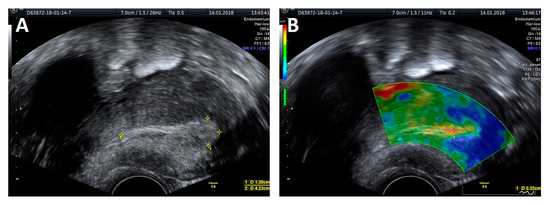

The protocol of endometrial investigation with elastography and a transvaginal probe was applied in all 69 patients (Figure 1 and Figure 2).

Figure 2. A 2D ultrasound presentation: endometrial thickness (A) and elastography: thickness measurement of the softest layer of the endometrium (B).